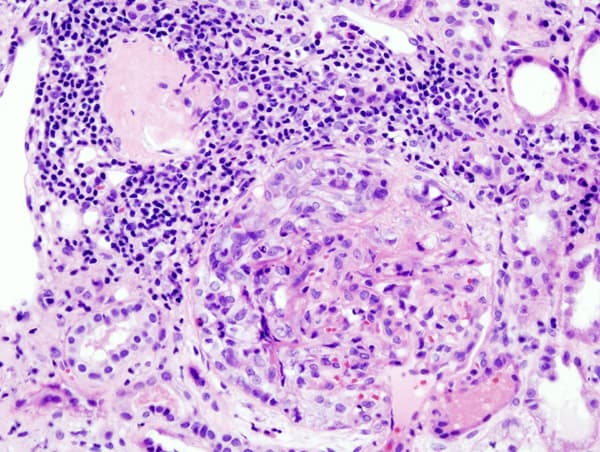

Rapidly progressive glomerulonephritis (RPGN) is a syndrome of the kidney that is characterized by a rapid loss of kidney function, (usually a 50% decline in the glomerular filtration rate (GFR) within 3 months) with glomerular crescent formation seen in at least 50% or 75% of glomeruli seen on kidney biopsies. If left untreated, it rapidly progresses into acute kidney failure and death within months. In 50% of cases, RPGN is associated with an underlying disease such as Goodpasture syndrome, systemic lupus erythematosus or granulomatosis with polyangiitis; the remaining cases are idiopathic. Regardless of the underlying cause, RPGN involves severe injury to the kidneys' glomeruli, with many of the glomeruli containing characteristic glomerular crescents (crescent-shaped scars). Most types of RPGN are characterized by severe and rapid loss of kidney function with marked hematuria; red blood cell casts in the urine; and proteinuria sometimes exceeding three grams in twenty-four hours, a range associated with nephrotic syndrome. Some patients also experience hypertension and edema. Severe disease is characterized by pronounced oliguria or anuria, which portends a poor prognosis. It is thought that antineutrophil cytoplasmic antibodies (ANCA) interact with antigens in the cytoplasm of neutrophils to cause an early degranulation, triggering the release of lytic enzymes at the site of injury and leading to the formation of glomerular crescents that consist primarily of parietal epithelial cells from Bowman's capsule and in some cases podocytes. Serum analysis often aids in the diagnosis of a specific underlying disease. The presence of anti-glomerular basement membrane (GBM) antibodies suggests type I RPGN; antinuclear antibodies (ANA) may support a diagnosis of systemic lupus erythematosus and type II RPGN; and type III and idiopathic RPGN are frequently associated with anti-neutrophil cytoplasmic antibodies (ANCA)-positive serum. Impaired kidney function in an individual who has had the condition for fewer than three months is characteristic of RPGN.